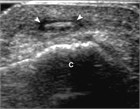

超音波ガイド下の除去法

ハンマーがノミ等の他の金属を打つと,中程度の速度で小さな金属片が飛ぶことがある.患者は刺すような痛みを感じて小さな刺創や出血に気づき,創の中に異物があるのではないかと心配する.BB弾はよりわかりやすく,同様の問題を引き起こすだろう.放射線不透過性の硬い異物として,他にはガラスの破片があり,特にガラスの破片を踏んでしまった場合や,自動車事故でガラス破片が飛んできた場合に受傷する.砂利の上に落ちた場合も,小さな刺創から鋭い破片が皮下に押し込まれることがある.身体所見では刺創が観察でき,その下に暗い変色部位や触知可能な異物がみられることがある.